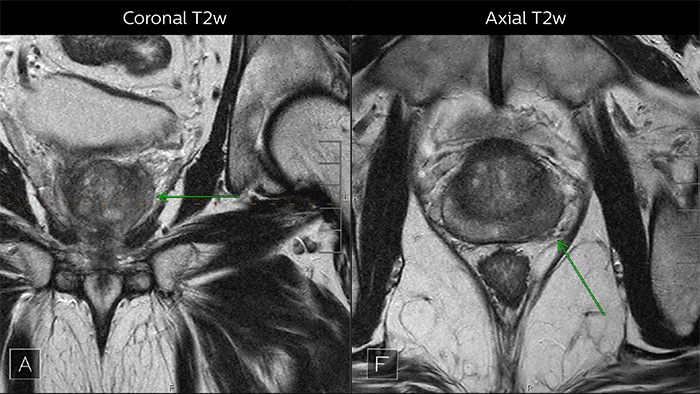

Depending upon the Gleason score and prior therapies, prostate carcinoma has a certain predictable pattern on multiparametric MRI, according to Dr. Steiner. “In general, lesions in the peripheral zone have decreased T2-weighted signal and are relatively focal,” he says. “In the transitional zone, these lesions are more difficult to evaluate on T1 and T2, but are generally non-encapsulated.”

Multiparametric MRI of a classic peripheral zone lesion Dr. Steiner describes this case: “For lesions in the peripheral zone of the prostate, the DWI (diffusion weighted imaging) and ADC map are most helpful for diagnosis. In this case, the DWI shows a very bright signal, which indicates diffusion restriction. The arcuate area with significant signal drop out (arrow) on the ADC map is recognized as highly suspect for tumor. On the axial T2-weighted image the capsule contour looks a little irregular (arrow), which we interpret as capsular disruption, and I usually give a measurement: this lesion shows larger than 1.5 cm capsular disruption. I don’t see any signs of lymphadenopathy, but interpret this lesion as PI-RADS 5. The hypervascular flow pattern in the bottom images adds to the diagnostic confidence.”